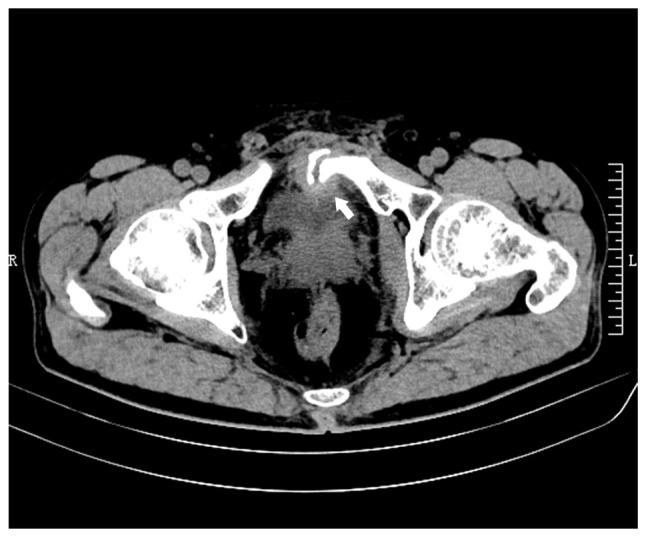

Pelvic fractures sometimes lead to injuries of the urinary bladder, which commonly present as gross hematuria, dysuria and lower abdominal pain. As a type of urinary stone, bladder stones are usually secondary to lower urinary tract obstruction, such as benign prostatic hyperplasia, urethral stricture, and neurogenic bladder. The present case report examines an unusual case of a delayed pubic fracture penetrating the bladder, which caused a secondary bladder stone. A 53-year-old man was first hospitalized at The Second Hospital of Jiaxing (Jiaxing, China) in January 2020 because of trauma-induced bleeding in the scalp and abdominal pain. The patient underwent abdominal exploration and partial bowel resection, and his condition stabilized after surgery. After discharge, the patient had regular outpatient check-ups every 2-3 weeks. However, after 3 months, in April 2020, the patient was readmitted to the hospital because of frequent urination, an urgent need for urination and dysuria. Abdominal computed tomography imaging and cystoscopy revealed a pubic fracture that had penetrated the bladder wall, accompanied by a bladder stone. Subsequently, cystolithotomy was performed, which provided significant relief of symptoms once the catheter was removed after 2 weeks. Since then, the patient has been followed up until January 2023 and had remained asymptomatic. Bladder stones caused by necrotic bone fragmentation are rare. Bladder injuries resulting from pelvic fractures can have delayed onset; therefore, clinicians should be aware of the possibility of urogenital injury in such patients. It is crucial for clinicians to comprehend the potential mechanisms involved, analyze the clinical data of patients, closely monitor their condition and implement appropriate treatment measures when necessary.

骨盆骨折有时会导致膀胱损伤,通常表现为肉眼血尿、排尿困难和下腹部疼痛。膀胱结石作为泌尿系统结石的一种,通常继发于下尿路梗阻,如良性前列腺增生、尿道狭窄和神经源性膀胱。本病例报告研究了一例罕见的耻骨骨折延迟穿透膀胱导致继发性膀胱结石的病例。一名53岁男性于2020年1月因创伤性头皮出血和腹痛首次入住嘉兴市第二医院(中国嘉兴)。患者接受了腹部探查和部分肠切除术,术后病情稳定。出院后,患者每2 - 3周进行一次定期门诊检查。然而,3个月后的2020年4月,患者因尿频、尿急和排尿困难再次入院。腹部计算机断层扫描成像和膀胱镜检查显示耻骨骨折穿透膀胱壁,并伴有膀胱结石。随后进行了膀胱切开取石术,术后2周拔除导尿管后症状明显缓解。此后,对患者进行随访直至2023年1月,患者一直无症状。由坏死骨碎片引起的膀胱结石很少见。骨盆骨折导致的膀胱损伤可能会延迟出现;因此,临床医生应意识到此类患者存在泌尿生殖系统损伤的可能性。临床医生理解其中潜在机制、分析患者临床数据、密切监测病情并在必要时采取适当治疗措施至关重要。